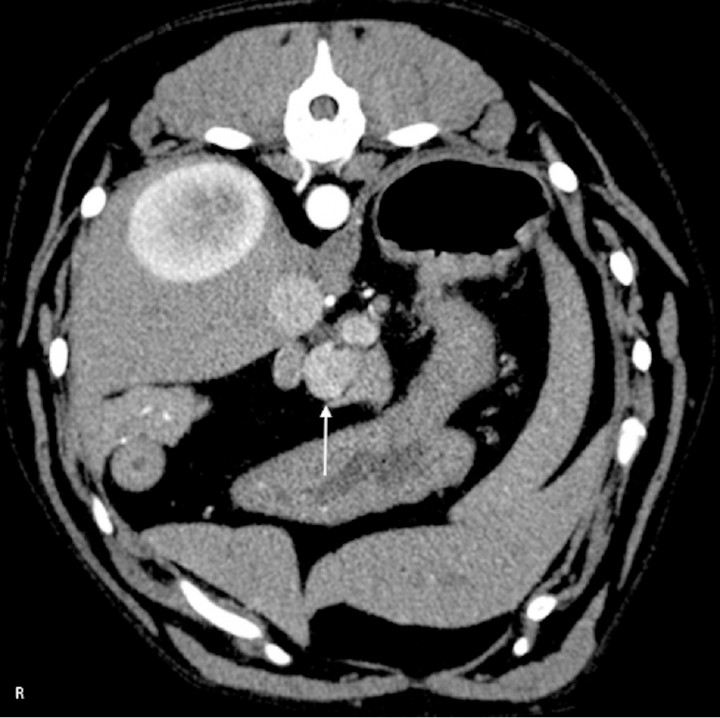

Angiographic CT techniques are also used to evaluate pancreatic insulinomas.[ Fukushima K, Fujiwara R, Yamamoto K et al.: Characterization of triple-phase computed tomography in dogs with pancreatic insulinoma. J Vet Med Sci 2016; 77(12):1549-1553. [PMC] ] Ultrasound is a good screening modality to evaluate the pancreas, however insulinomas, mainly represented by small hypoechoic nodules, have been described challenging to image. Ultrasound is highly dependent on imaging skills of the ultrasonographer and accessibility of the pancreas, however is less cost intensive than CT and does not requires anesthesia.[ Nakamura K, Lim S-Y, Ochiai K et al.: Contrast-enhanced ultrasonographic findings in three dogs with pancreatic insulinoma. Vet Radiol Ultrasound 2015; 56:55-62. [PubMed] ] The big advantage of CT is that offers multiplanar reconstruction, which is especially helpful in a small and anatomically challenging organ, and that angiographic CT techniques maximize the conspicuity of small pancreatic messes. A report of three dogs with insulinoma found that these masses showed a strong contrast enhancement that was present during the arterial phase (Fig. 7).[ Nakamura K, Lim S-Y, Ochiai K et al.: Contrast-enhanced ultrasonographic findings in three dogs with pancreatic insulinoma. Vet Radiol Ultrasound 2015; 56:55-62. [PubMed] ] However, it has lately been reported to show variable attenuation patterns ranging from being hyperattenuated in the arterial phase to also being hypoattenuated in some cases.[ Fukushima K, Fujiwara R, Yamamoto K et al.: Characterization of triple-phase computed tomography in dogs with pancreatic insulinoma. J Vet Med Sci 2016; 77(12):1549-1553. [PMC] ]

<p>CT angiogram transverse soft tissue window image in arterial post contrast phase of an 8 year-old German Pinscher. There is a rounded, contrast enhancing mass (white arrow) at the level of the pancreatic body, compatible with an insulinoma. The mass is hyperattenuating to the pancreas during the arterial phase. R: right.</p>

CT angiogram transverse soft tissue window image in arterial post contrast phase of an 8 year-old German Pinscher. There is a rounded, contrast enhancing mass (white arrow) at the level of the pancreatic body, compatible with an insulinoma. The mass is hyperattenuating to the pancreas during the arterial phase. R: right.